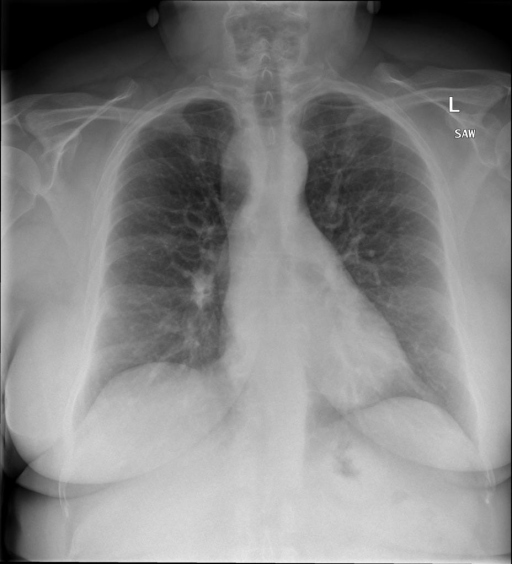

## 本文贡献  - 借助ChatGPT以及公开的数据集,我们构造了一个`X光影像-诊断报告`对的医学多模态数据集; - 我们将构建的中文胸部X光片诊断数据集在[VisualGLM-6B](https://github.com/THUDM/VisualGLM-6B)进行微调训练,并开放了部分训练权重用于学术研究; ## 数据集 - [MIMIC-CXR](https://physionet.org/content/mimic-cxr-jpg/2.0.0/)是一个公开可用的胸部X光片数据集,包括377,110张图像和227,827个相关报告。 - [OpenI](https://openi.nlm.nih.gov/faq#collection)是一个来自印第安纳大学医院的胸部X光片数据集,包括6,459张图像和3,955个报告。 在上述工作中,报告信息都为非结构化的,不利于科学研究。为了生成合理的医学报告,我们对两个数据集进行了预处理,并最终得到了可以用于训练的**英文报告**。除此之外,为了更好的支持中文社区发展,借助ChatGPT的能力,我们将英文报告进行了中文翻译,并最终形成了可用于训练的数据集。 |数据集|数量|下载链接| |:-|:-|:-| |MIMIC-CXR-zh|-|-| |OpenI-zh|6,423|[诊疗报告(英文)](./data/openi-en.json)、[诊疗报告(中文)](./data/Xray/openi-zh.json) 、[X光影像](https://pan.baidu.com/s/13GBsDMKf6xBZBSHpoWH_EA?pwd=k9sh)| ## 快速上手 1. 安装环境 ```bash # 安装依赖 pip install -r requirements.txt # 国内换源安装依赖 pip install -i https://mirrors.aliyun.com/pypi/simple/ -r requirements.txt ``` 此时默认会安装`deepspeed`库(支持`sat`库训练),此库对于模型推理并非必要,同时部分`Windows`环境安装此库时会遇到问题。 如果想绕过`deepspeed`安装,我们可以将命令改为: ```bash # 安装依赖 pip install -i https://mirrors.aliyun.com/pypi/simple/ -r requirements_wo_ds.txt # 安装SwissArmyTransformer pip install -i https://mirrors.aliyun.com/pypi/simple/ --no-deps "SwissArmyTransformer>=0.3.6" ``` 2. 模型推理 |模型权重|下载链接| |:-|:-| |checkpoints-XrayGLM-300|-| |checkpoints-XrayGLM-3000|-| CLI推理: ```python python cli_demo.py --from_pretrained checkpoints/checkpoints-XrayGLM-3000 --prompt_zh '详细描述这张胸部X光片的诊断结果' ``` 更多[参数](https://github.com/WangRongsheng/XrayGLM/blob/main/cli_demo.py#L16) ## 效果展示 影像诊断: |X光影像|诊疗报告(医生)|XrayGLM| |:-|:-|:-| ||根据X射线图像,心脏大小正常,肺部看起来很清晰。已经排除了肺炎、积液、水肿、气胸、腺病、结节或肿块的存在。该发现表明一切正常。换句话说,总体印象是胸部正常。|X光片显示,心脏大小正常。肺部没有气胸或胸腔积液的证据。骨骼结构看起来没有任何异常。总的来说,X光片表明没有发现急性心肺疾病的迹象。| ||X光图片显示没有扭曲的区域、可疑的骨质不透明度或胸腺积液。心脏大小轻微增大,但非常稳定。此外,没有气胸的证据,肺野也正常。总体来说,X光片显示没有急性心脏异常,但要注意轻微的心脏扩大。|X光片显示,心脏大小正常。肺部和纵隔轮廓清晰,没有气胸或胸腔积液的证据。骨骼结构完整,没有任何急性异常。| ||心影形态在正常范围内。没有急性骨质异常。有可能出现没有明显的吸水或肺实质状况的线索。没有大面积积液或气胸。有可能怀疑其有误吸或肺实质问题。为了确诊和治疗,可能需要进行适当的影像学随访。|心脏大小正常,肺部和纵隔轮廓清晰。没有急性异常或活动受限的证据。没有任何明显的气胸、胸腔积液或肺不张的迹象。此外,也没有发现任何局灶性骨质异常或其他急性疾病。| 多轮对话: |X光影像|诊疗报告(医生)| |:-|:-| ||右侧主动脉突出观察到。心脏大小正常。胸部未发现明显的肺气肿、胸膜积液或可疑的肺部病变。报告指出已知右侧主动脉情况正常。| ```bash >> X光影像路径:./data/Xray/861_1.png >> 用户:这是一张什么图? >> XrayGLM:这张图片显示的是一张肺部检查的X光片。 >> 用户:请描述这张胸部X光片的诊断结果 >> XrayGLM:心脏大小正常,肺部清晰。没有急性心肺疾病的证据。 >> 用户:是否存在肺气肿? >> XrayGLM:没有肺气肿。心脏大小正常,肺部清晰。没有发现急性心肺疾病的证据。 >> 用户:平时饮食该注意什么? >> XrayGLM:饮食应该健康,均衡。建议增加蛋白质的摄入量,因为蛋白质有助于维持肌肉和骨骼的健康。多食用蔬菜、水果、全谷物以及健康的脂肪来源如橄榄油、鱼类等可以帮助获得足够的维生素和矿物质。此外,避免过度饮酒或吸烟,这些习惯可能会对心脏健康产生负面影响。 ``` ## 未来展望 1. 模型的能力更多来源于数据的支持,`OpenI-zh`作为微调数据集,其数据量足以支持研究,在更广泛的任务和性能表现上,我们认为**在大规模数据集上预训练并在高质量少量数据集上微调是一种可行的方案**; 2. 普遍意义的理解上,视觉多模态模型=视觉模型+语言模型。除了需要关注视觉模型信息与语言模型输出的搭配外,还需要**额外关注到语言模型的加强,在人机的对话中,尤其是医疗语言模型的问答上,除了专业的医疗问题回答,带有人文情怀的有温度的回答更应该是我们追寻的目标**。 ## 项目致谢 1. [VisualGLM-6B](https://github.com/THUDM/VisualGLM-6B)为我们提供了基础的代码参考和实现; 2. [MiniGPT-4](https://github.com/Vision-CAIR/MiniGPT-4)为我们这个项目提供了研发思路; 3. ChatGPT生成了高质量的中文版X光检查报告以支持XrayGLM训练; 4. [gpt_academic](https://github.com/binary-husky/gpt_academic)为文档翻译提供了多线程加速; 5. [MedCLIP](https://github.com/RyanWangZf/MedCLIP) 、[BLIP2](https://huggingface.co/docs/transformers/main/model_doc/blip-2) 、[XrayGPT](https://github.com/mbzuai-oryx/XrayGPT) 等工作也有重大的参考意义;  这项工作由[澳门理工大学应用科学学院](https://www.mpu.edu.mo/esca/zh/index.php)硕士生[王荣胜](https://github.com/WangRongsheng) 、[段耀菲](https://github.com/IsBaSO4) 、[李俊蓉](https://github.com/lijunrong0815)完成,指导老师为檀韬副教授、[彭祥佑](http://www.patrickpang.net/)老师。 *特别鸣谢:[USTC-PhD Yongle Luo](https://github.com/kaixindelele) 提供了有3000美金的OpenAI账号,帮助我们完成大量的X光报告翻译工作 ## 免责声明 本项目相关资源仅供学术研究之用,严禁用于商业用途。使用涉及第三方代码的部分时,请严格遵循相应的开源协议。模型生成的内容受模型计算、随机性和量化精度损失等因素影响,本项目无法对其准确性作出保证。即使本项目模型输出符合医学事实,也不能被用作实际医学诊断的依据。对于模型输出的任何内容,本项目不承担任何法律责任,亦不对因使用相关资源和输出结果而可能产生的任何损失承担责任。 ## 项目引用 如果你使用了本项目的模型,数据或者代码,请声明引用: ```bash @misc{wang2023XrayGLM, title={XrayGLM: The first Chinese Medical Multimodal Model that Chest Radiographs Summarization}, author={Rongsheng Wang, Yaofei Duan, Junrong Li, Patrick Pang and Tao Tan}, year={2023}, publisher = {GitHub}, journal = {GitHub repository}, howpublished = {\url{https://github.com/WangRongsheng/XrayGLM}}, } ``` ## 使用许可 此存储库遵循[CC BY-NC-SA](https://creativecommons.org/licenses/by-nc-sa/4.0/) ,请参阅许可条款。